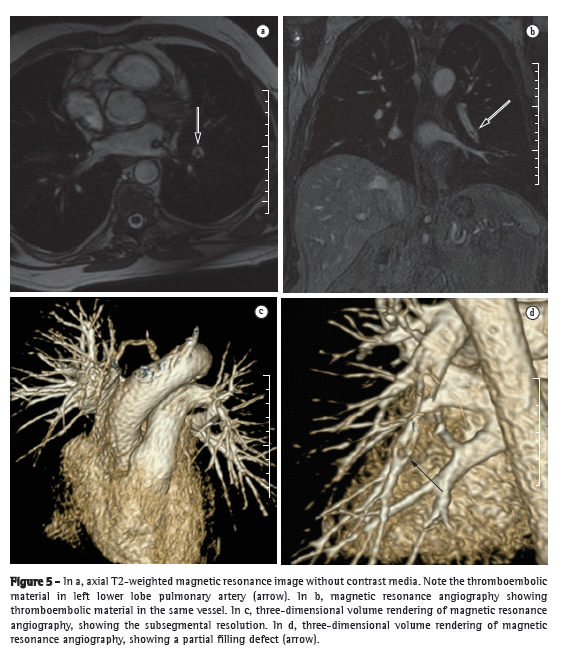

Substantial technical advances in pulmonary MRA have been introduced in recent years (Figures 5 and 6). Continued improvements are ongoing and include the use of parallel imaging, view sharing, time-resolved echo-shared angiography,(17-19) and pulmonary perfusion. These techniques have shortened MRA acquisition time, made it less susceptible to motion artifacts, and improved spatial resolution. One study showed that a combined magnetic resonance protocol (progressing from real-time MRI to perfusion MRI to MRA) is reliable and sensitive, producing results similar to those obtained with 16-slice multidetector CT.(18)

In 2003, Stein et al.(20) conducted a meta-analysis of the use of gadolinium-enhanced MRI for the depiction of acute pulmonary embolism. The authors used conventional pulmonary angiography as the reference standard. They found that the reported sensitivity of the procedure covered a broad range (77-100%) and that the reported specificity was uniformly high (95-98%).(20) In the most recent of the studies evaluated in that meta-analysis, Oudkerk et al.(21) showed that the sensitivity of contrast-enhanced MRI for pulmonary embolism was 100% in the central and lobar arteries; 84% in the segmental arteries; and only 40% in the subsegmental branches.

In cases of suspected acute pulmonary embolism, MRI with a state-of-the-art, three-component protocol (true fast imaging with steady-state precession; perfusion; and MRA with parallel acquisition) has recently been shown to be highly accurate.(18) The reported per-patient sensitivity and specificity, respectively, are 85% and 98% for the true fast imaging sequence; 100% and 91% for the perfusion sequence; and 77% and 100% for the MRA. The combined protocol has a reported sensitivity of 100% and a reported specificity of 93%. Although MRI and MRA are specific, they have low sensitivity, particularly for subsegmental pulmonary embolism. Overall, the combined MRI protocol has been found to be more reliable and sensitive than is 16-slice multidetector CT.(18) The average MRI examination time is reported to be approximately 10 min.(18)